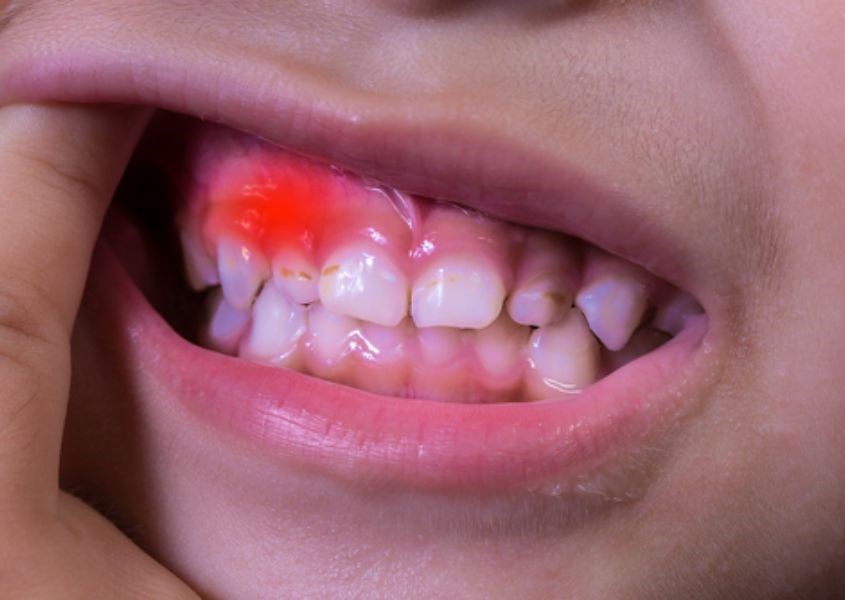

Nướu khỏe mạnh là nướu căng, có màu hồng, không bị chảy máu và không bị đau khi nhai. Khi nướu sưng lên, chúng có màu đỏ tấy và dễ bị chảy máu khi tác động mạnh vào vị trí bị sưng. Trong một số trường hợp nghiêm trọng, nướu còn có xu hướng sưng lên đến mức che lấp một phần răng của trẻ.

Viêm nướu răng: Viêm nướu thường xảy ra khi răng làm rách nướu và trào ra khoang miệng. Nhưng nếu trong trường hợp vệ sinh răng miệng kém, tình trạng viêm nhiễm này có thể trở nên trầm trọng hơn, dẫn đến viêm nướu răng mọc. Tình trạng này sẽ giảm dần xuống khi việc vệ sinh răng miệng được cải thiện hơn.

Viêm nướu răng ở trẻ. Nguồn từ drnemeth